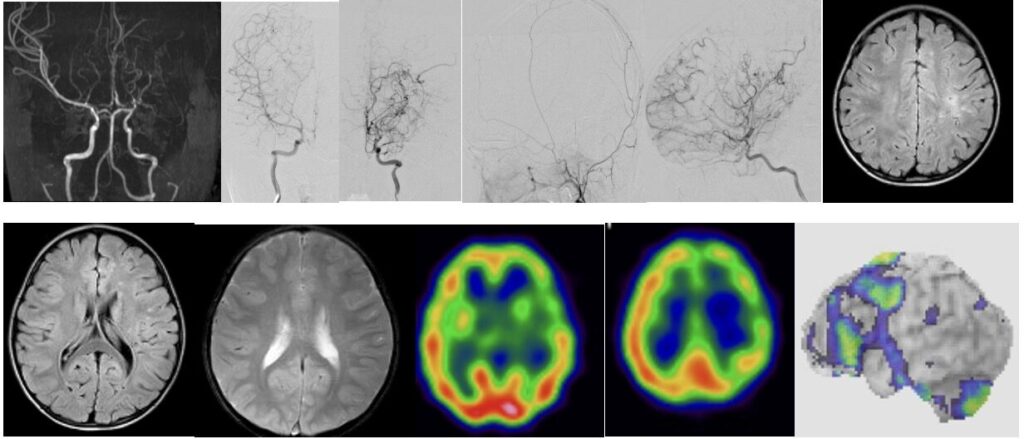

- もやもや病

1991年京都大学医学部卒業。顕微鏡手術の日本の開祖、菊池晴彦教授が主宰する京都大学脳神経外科に入局。脳血管バイパス術を習得し卒後3年目よりもやもや病執刀を許可される。1992年より大津赤十字病院救急救命センターに赴任し高度救急医療に従事。1994年より京都大学大学院に進学。第一薬理学教室(真崎知生教授:エンドセリン)で血管内皮に関する研究により医学博士を取得。1998年より倉敷中央病院(山形専部長)に赴任し脳動脈瘤と頸動脈手術を習得。2000年より京都大学(橋本信夫教授)に帰学。脳動静脈奇形、(AVM)、脳腫瘍などメジャー手術の指導を受け、もやもや病研究班にも参加。2009年福井大学脳神経外科教授に着任。福井に京大流の高度な脳血管外科を導入。2017年より7年間福島孝徳教授のもとで聴神経腫瘍、頭蓋底腫瘍、鍵穴手術の直接指導を受ける。2021年から外視鏡手術を導入。京大流と福島流の手術技術に、術中画像などテクノロジーを組み合わせ、技術革新を行い、常に新しい手術を創造し、成績向上と後進の育成に勤めている。